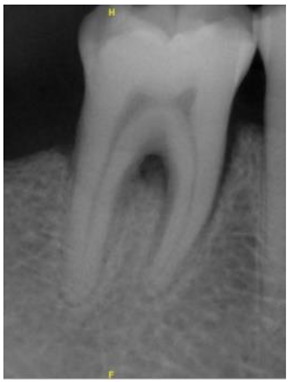

| Original Images | Gaussian High-Pass Filter | Gaussian High-Pass Filter + Mask | |

|---|---|---|---|

| Validation Accuracy | 84.16% | 87.21% | 94.97% |

| Validation Loss | 0.7634 | 0.4578 | 0.1822 |

| Image | ![]() | ![]() | ![]() |